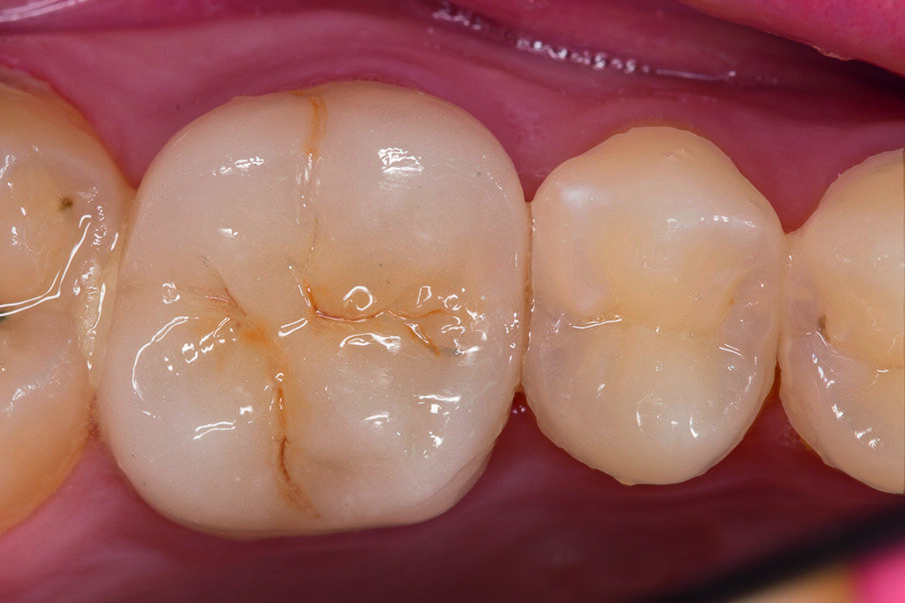

This case below shows a posterior tooth with an endodontic treatment followed by an indirect crown restoration. SDR® Plus is used as a core build up material before the crown was seated.

This case involves the use of SDR® Plus composite as a core build-up material. The outstanding flowability of SDR® Plus composite allows complete filling of the pulp cavity, even in the smallest recesses; the composite was placed in two stages to ensure thorough polymerisation. The periphery of the tooth was then prepared, preserving a layer of enamel at the preparation margin to ensure effective bonding of an all-ceramic crown. This was bonded with the Calibra® system. This protocol thus avoids iatrogenic mechanical strains on the tooth roots during core build-up. This treatment, involving a tooth/restoration monoblock with SDR® Plus composite and crown using only adhesive techniques, provides for outstanding biomechanical and aesthetic results.

Fig. 6: View of the tooth – with the SDR® Plus core prepared for crown seating..